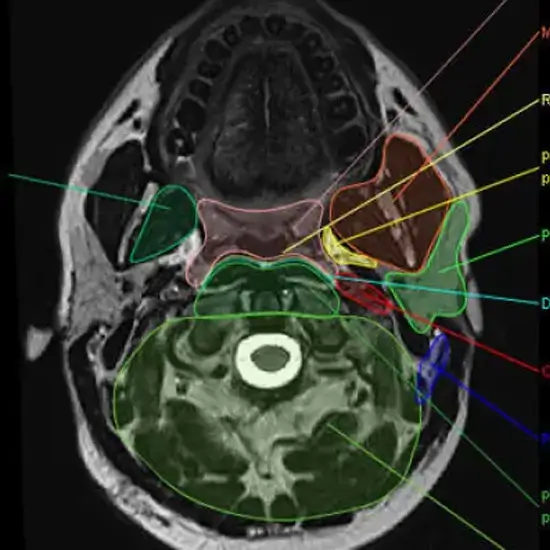

The MRI Face and Neck show the face and neck structures. It identifies diseases of soft tissue, blood vessels, or bone. MRI of the neck can detect spinal cord damage and tumours.

MRI (Magnetic Resonance Imaging) spine is a non-invasive medical diagnostic tool used to obtain detailed images of the face, neck and surrounding tissue. MRI of the face and neck is used to show abnormalities like neck and face fractures, injuries, inflammations etc.